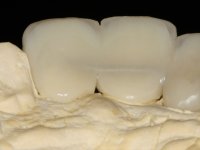

Endodontic treatments were performed and a metalic non screwed intra radicular post was placed on tooth 1.1. An alginate impression was made for laboratory confection of a reinforced acrylic provisional bridge, with teeth 1.1 and 2.2 as abutments and 2.2 as a pontic. After preparation of tooth 1.1 and root preparation of 2.1, the bridge was relined in mouth with self-polymerizable acrylic using a metal post for further retaining the prepared root canal on 2.1. Tooth 2.2 was cut at the gingival level to function as support. In the same session, the impression of the root canal of the 2.1 was made for the laboratory confection of a cast post and core. A double mixture technique with plastic tutor was used after previous canal vaseline with endodontic file and cotton. The provisional bridge was provisionally cemented and the cast post and core was made in the laboratory. Cast post and core cementation was made with resin-reinforced glass ionomer cement and the provisional bridge had to be readjusted to the new situation by removing the post at the site of 2.1. After careful surgical planning, a dental implant was placed, simultaneously with extraction of the root of tooth 2.2. The provisional bridge was placed by resting on the healing screw placed in the implant. The respected osteointegration period was 12 weeks, during which the provisional bridge was relined twice. After complete maturation of hard and soft tissues, definitive impressions were made. The gingival retraction technique was applied with an impregnated retraction cord and impression was performed using double mixture, open tray impression technique. A custom precious metal abutment implant was prepared in the lab, along with 3 metal caps to be used as infrastructures for the metal ceramic crowns. Particular care was taken in the confection of the cervical finishing line of the implant abutment, in order to follow the soft tissues emergence profile. Proof of infrastructures was done in the mouth being evaluated clinically and imagiologically. Collection of color information was done by the ceramist at the office. Ceramic was applied in the laboratory and the finished work was placed in the mouth after approval by the patient. Definitive cementation was made with resin-reinforced glass ionomer cement, and the first crown to be cemented was that of the implant, to facilitate removal of the excess.